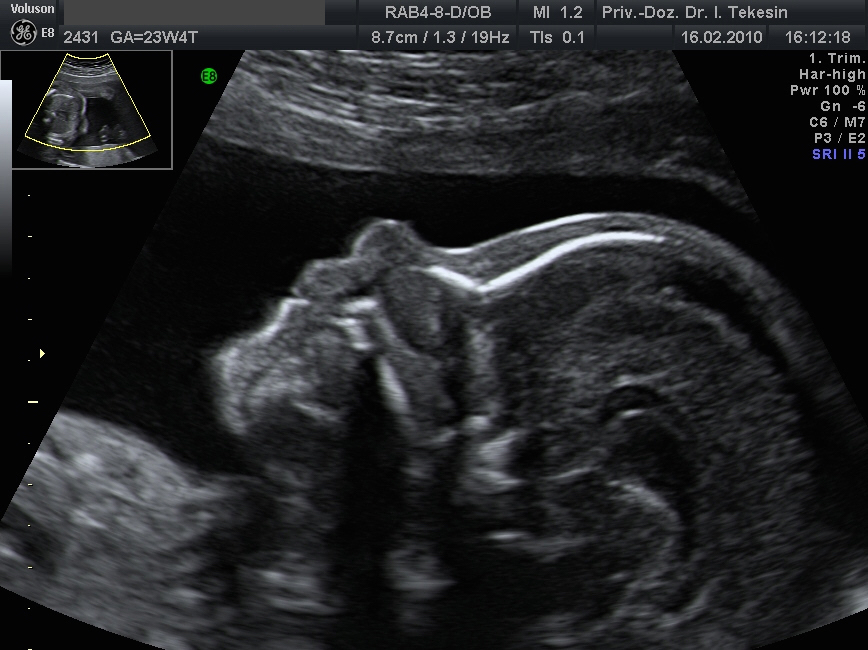

Normaler Vierkammer-Blick mit Farbe

Normales Herz in der 22. Woche